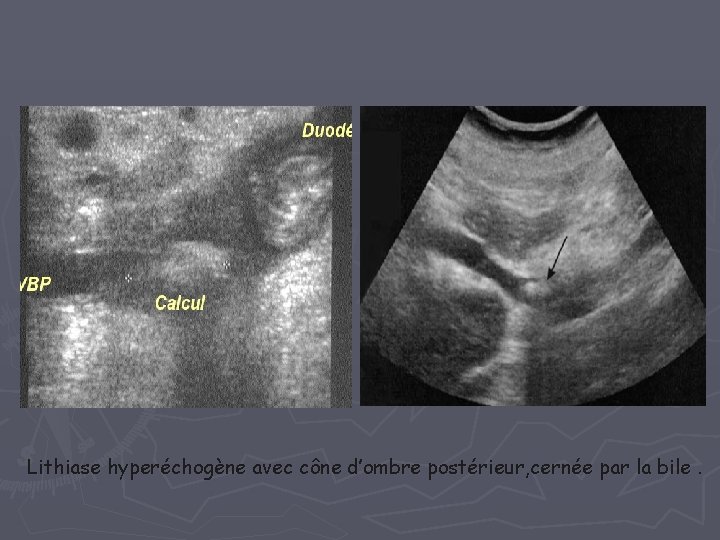

I- Dilatation des voies biliaires intra et extra hépatiques =obstacle au niveau du carrefour bilio-pancréatique 1 - Pathologie lithiasique Cause la plus fréquente Complique les lithiases vésiculaires Clinique: Ictère + douleur + fièvre Écho : Dilatation de la VBP Lithiase : matériel hyper échogène + cône d’ombre postérieur Lithiases vésiculaires +++

Lithiase hyperéchogène avec cône d’ombre postérieur, cernée par la bile.